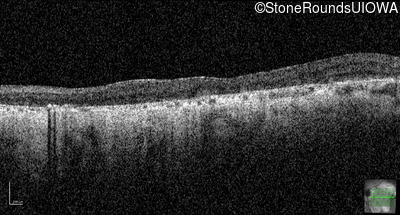

Optical Coherence Tomography - Left - 20/200

Exemplar / OCT Stack